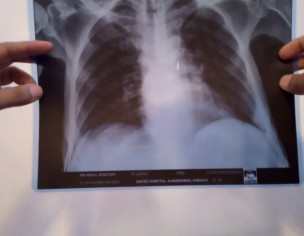

Patient was admitted in hospital due to cancer illness. He didnt have any fever or cough. The doctors performed chest X ray and determined on basis of X ray that patient has contracted coronavirus. I have attached the pictures of the X ray. Please verify if lungs are clear or not.

not necessary that all the patients of cancer have covid 19 but now a days it is nesccery to perform covid test of every immnocompromiz pt. Cancer is one of them . X ray chest is not normal but i m not an xray specialist. All the immunocompromised are nesccery to perform this test and indications to take precautions for doctos . If the test is positive than inform the relatives.